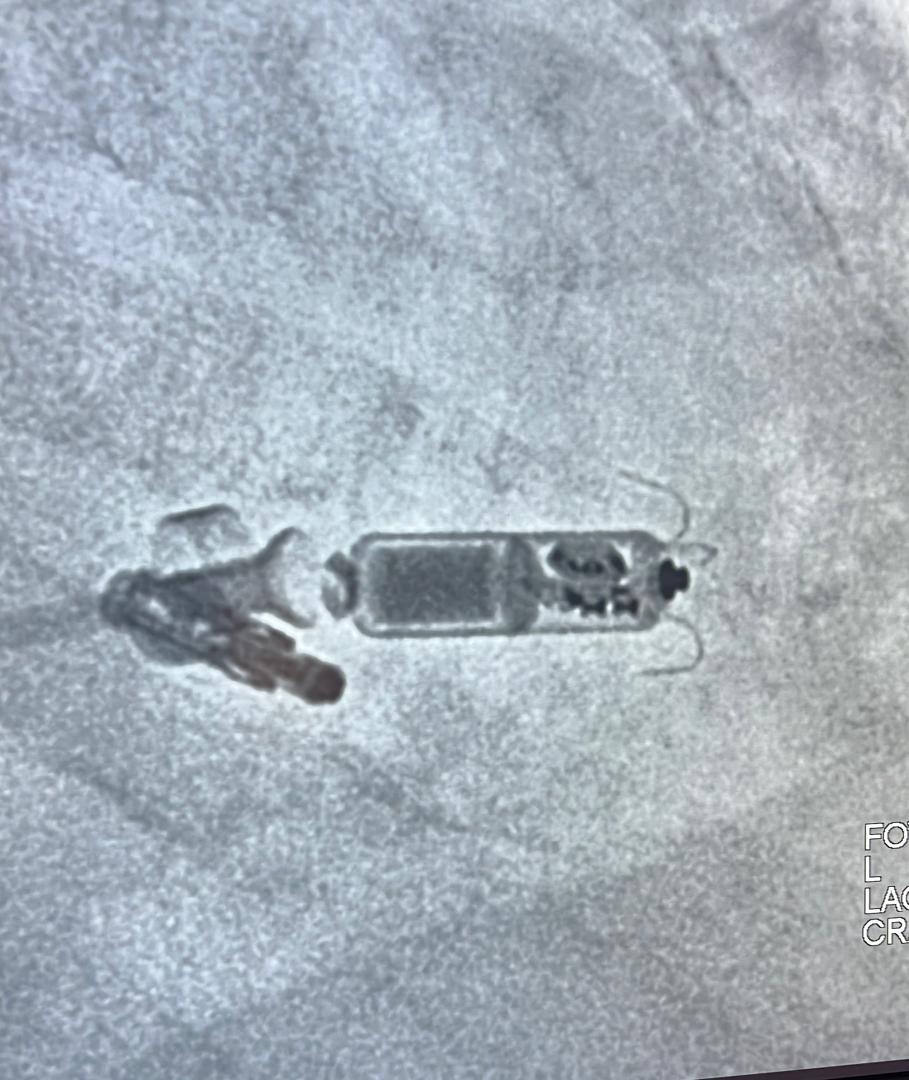

Thrilled to share that the EMBOL-AF Registry (>450 embolic complications of AF ablation) has been accepted for a LBCT session at EHRA 2025!